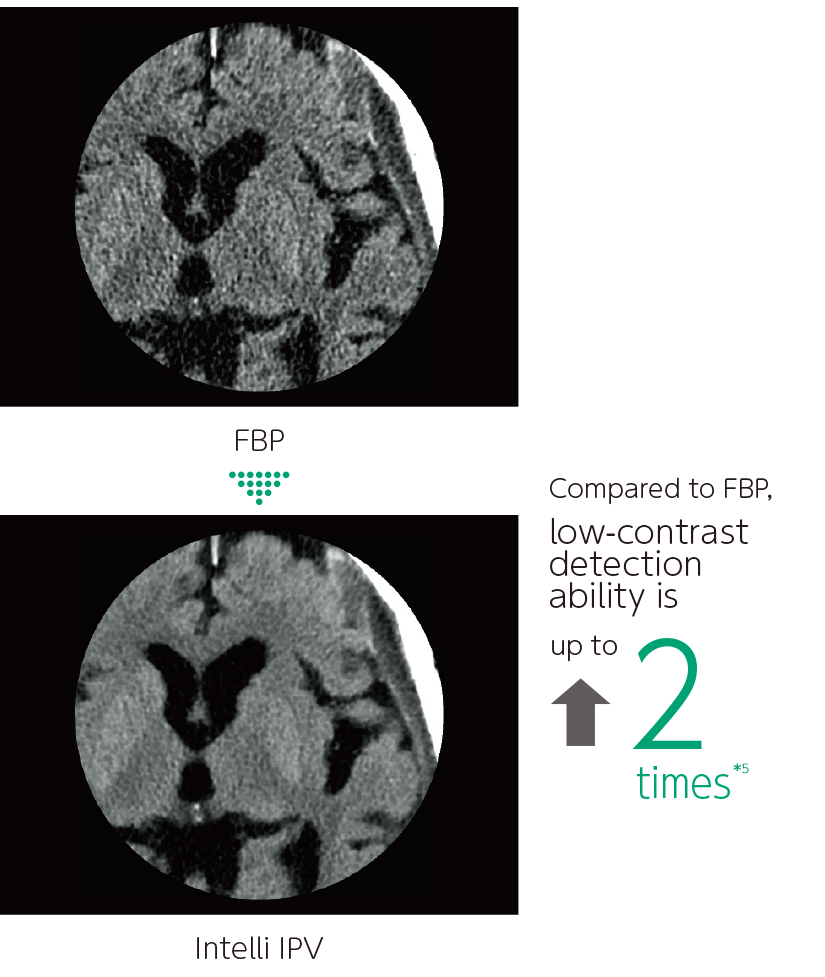

Intelli IPV is an image reconstruction technique developed with AI technology*3. Reconstruction processing has been speeded up by using images obtained through sufficient iterative processing as training data. Based on the Fujifilm's Visual Model, reconstruction processing using RawData brings the NPS(Noise Power Spectrum)closer to FBP(Filtered Back Projection)and keeps the image texture, even at a high noise reduction rate. It reduces image noise by up to 90%*4 and radiation exposure by up to 83%.*5 It also improves low contrast detectability by up to 2 times.*5

- *4 Compared to FBP. It was measured using Intelli IPV intensity level Strong5 and tested to a water phantom. Depending on the clinical task, patient size, anatomic location, and clinical examination, the effect obtained may be smaller.

- *5 Compared to FBP. It was measured at 0.625 mm slice thickness using Intelli IPV intensity level Strong5 and tested to MITA CT IQ phantom CCT189, Phantom Laboratory using the model observer method results. Depending on the clinical task, patient size, anatomic location, and clinical examination, the effect obtained may be smaller.